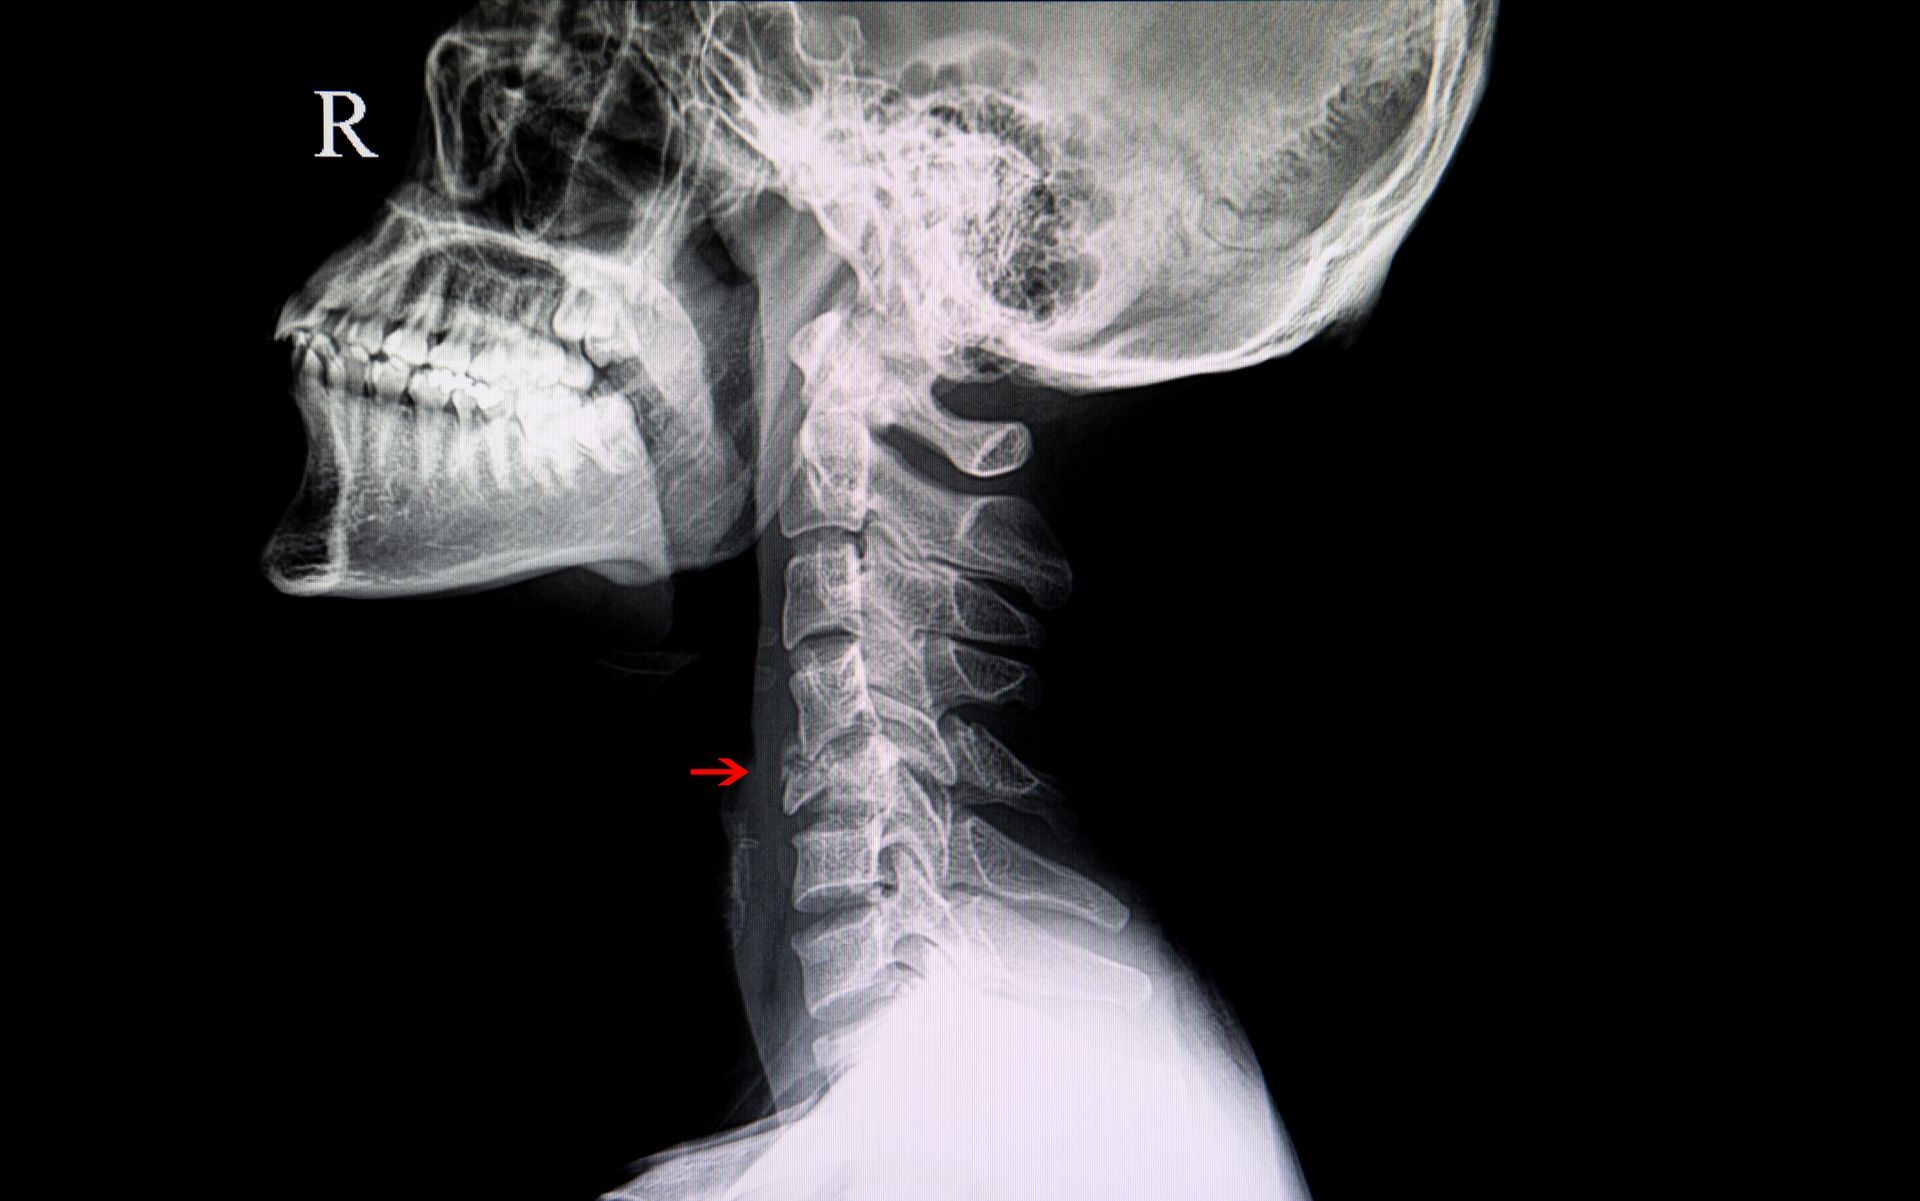

Ortopedia e Cirurgia da Coluna